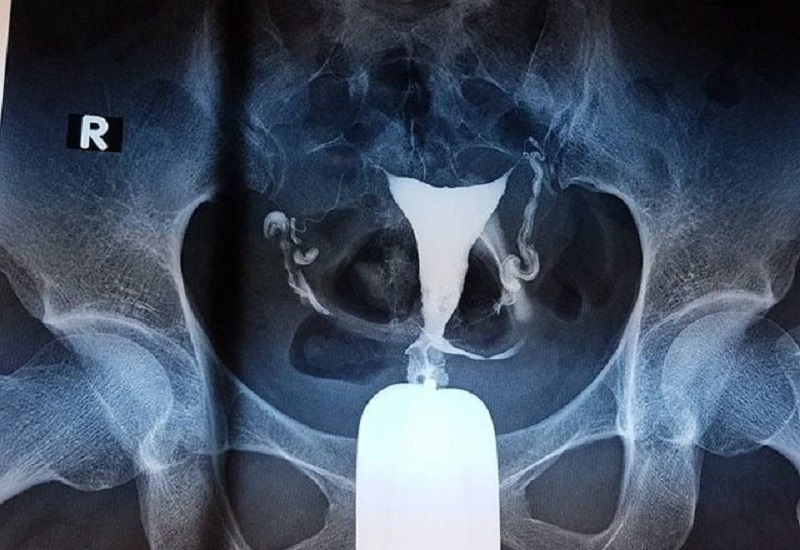

Về mặt kỹ thuật, HSG tương tự như chụp X-quang thông thường nhưng có bổ sung thêm thuốc cản quang. Thuốc này được đưa vào buồng tử cung thông qua cổ tử cung dưới áp lực nhẹ. Nhờ buồng tử cung thông trực tiếp với hai vòi trứng, thuốc cản quang sẽ lan tỏa sang cả hai bên vòi trứng. Hình ảnh chụp tại nhiều thời điểm khác nhau sẽ giúp bác sĩ quan sát quá trình di chuyển của thuốc, từ đó phát hiện những bất thường tại cổ tử cung, buồng tử cung, vòi trứng hoặc buồng trứng.

– Đánh giá tình trạng vòi trứng: Khi có nghi ngờ tắc nghẽn, dính, xoắn ống dẫn trứng – những nguyên nhân phổ biến gây cản trở quá trình thụ thai tự nhiên.

Nhờ khả năng cung cấp hình ảnh trực quan, rõ nét, chụp X-quang tử cung vòi trứng là một công cụ quan trọng trong quá trình khảo sát, chẩn đoán và đưa ra hướng điều trị phù hợp cho những người đang gặp vấn đề về sinh sản.

Chụp Xquang tử cung vòi trứng giúp đánh giá tình trạng vòi trứng